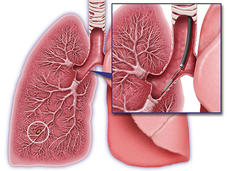

Uso de la expresión génica para diagnosticar de forma más precisa el cáncer de pulmón

Un patrón de expresión génica en las células de las vías respiratorias altas de pacientes con sospecha de cáncer de pulmón puede ayudar a diagnosticar el cáncer de pulmón de forma más precisa que la broncoscopia sola.